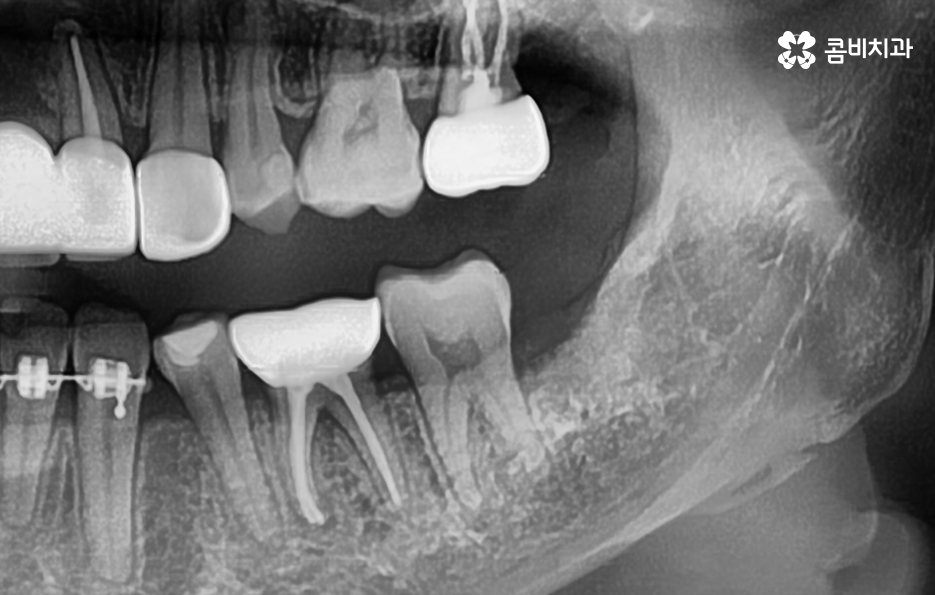

사랑니는 치아 중에서도 가장 마지막에 맹출이 되며 현대인들은 턱뼈가 좁아지는 추세이기 때문에 마지막에 자라는 사랑니는 위 케이스처럼 윗니의 경우 어금니의 높이 보다 다소 낮게 자라는 경우가 많고 아랫니의 경우 매복되어 있거나 누워서 자라는 사랑니의 형태로 자라는 경우가 많이 있는데요. 이러한 사랑니의 형태로 인해 어금니와 사랑니 사이에 이물질이 끼기 쉽고 칫솔질이 잘 닿지 않기 때문에 충치 뿐 아니라 잇몸 염증이 발생되는 경우가 많으며 사랑니 어금니 통증의 원인이 주변의 세균 증가로 인해 충치로 이가 썩은 경우부터 잇몸이 자주 붓고 염증이 심해지면서 통증을 느끼는 경우가 40,50대 이후에 흔하게 발생되는 사랑니와 인접한 어금니의 문제로 볼 수 있어요

일반적으로 30대 이후에는 치주질환이 급증하게 되는데 40,50대 이후에는 잇몸이 점점 내려 앉게 되고 부분적으로 맹출된 사랑니 주변 잇몸 역시도 조금씩 내려앉는 경우가 많이 있는데요. 사랑니 사진을 보시면 아시겠지만 일반적인 치아의 높낮이와는 달리 사랑니가 어금니의 뿌리 부분 정도 높이에 자리하고 있는 것을 볼 수 있어요.

일반적인 치아와 치아 사이는 이물질이 쉽게 침투하지 못하게 치아 사이의 공간이 많지 않고 치아 역시도 실링이 되어 있어서 미생물이 치아를 쉽게 뚫지 못하며 면역 물질로 인한 면역 작용도 있기 때문에 평소 칫솔질과 치실 사용, 주기적인 스케일링으로 어느정도 관리가 될 수 있는 것에 반하여 사랑니의 경우 어금니의 뿌리 부분에 가깝게 충치가 발생하기 쉽기 때문에 적절한 치료 시점을 놓치면 사랑니 어금니 통증이 두 치아 모두를 발치하게 되는 상황까지 발생될 수 있어요